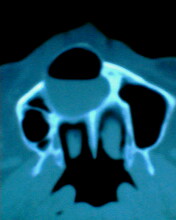

患者:男71岁,右侧上颚肿物无痛性生长7年.

右上颌骨近中线部见类圆形低密度区,上方见一液平,周围见一薄硬化环,前下方见一牙根,后方累及水平板。上方突入鼻腔前下部,下方突入口腔。

考虑:右侧上颌骨囊肿伴感染。

应诊断为右上颌骨含齿囊肿。